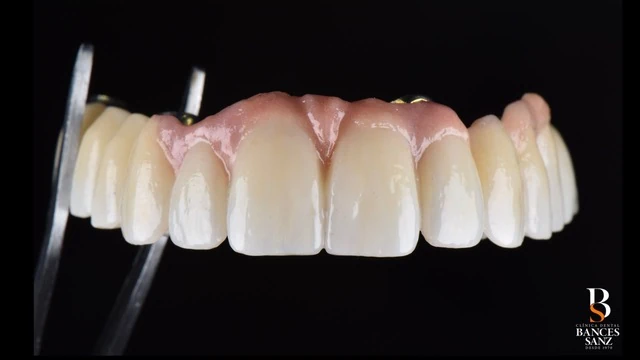

La planificación permitió realizar una carga inmediata, de forma que el paciente disponía de prótesis provisionales de alta estética en un plazo de 24–48 horas tras la intervención quirúrgica.

- Una estética excelente, incluso en las prótesis provisionales.

- Mejorar de forma notable la estética de la sonrisa.